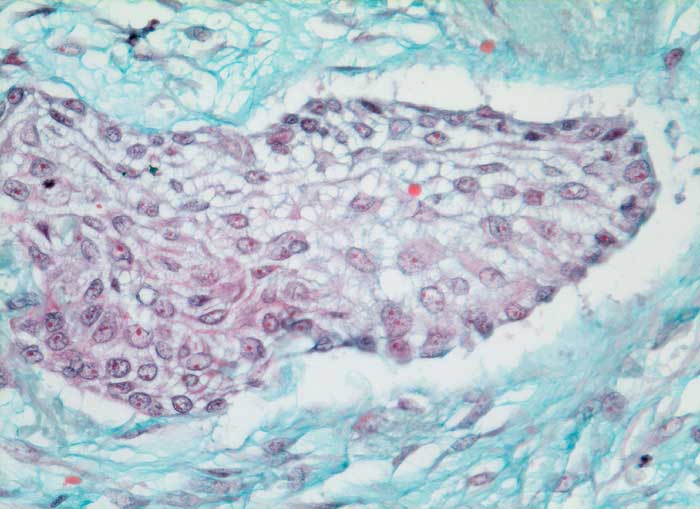

mässig differenziertes Plattenepithelkarzinom

Lunge

Solider Tumorzellverband ohne erkennbare Verhornung. Die Desmosomen zwischen den Zellen sind sehr gut erkennbar. Reichlich desmoplastisches Stroma.

Histologie

320